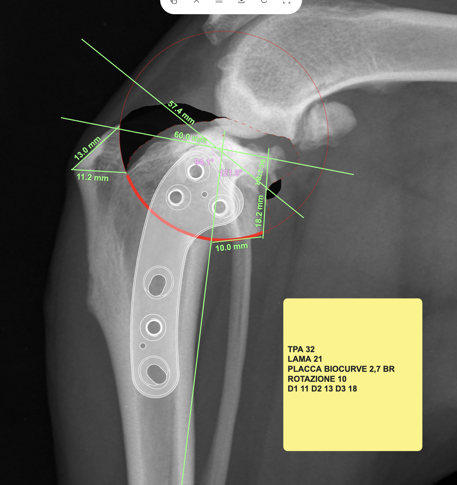

Quando necessario, il veterinario utilizza esami di imaging come le radiografie, utili per valutare ossa e articolazioni, oppure tecniche più avanzate come ecografie, TAC o risonanza magnetica, che consentono di studiare in modo più dettagliato tessuti molli, legamenti e strutture interne.